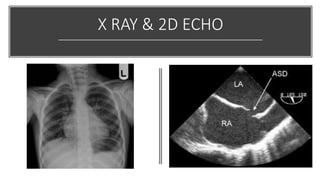

CHEST X-RAY

& 2D ECHO

REFLECT LARGE QP/QS

RV ENLARGEMENT

RA ENLARGEMENT

PLETHORIC PULMONARY FIELDS

ECHO CAN GIVE DIRECT EVIDENCE OF ASD, RVVO, AND

CHAMBER DIMENSIONS, ALONG WITH THE DIRECTION

OF THE SHUNT

X RAY & 2D ECHO